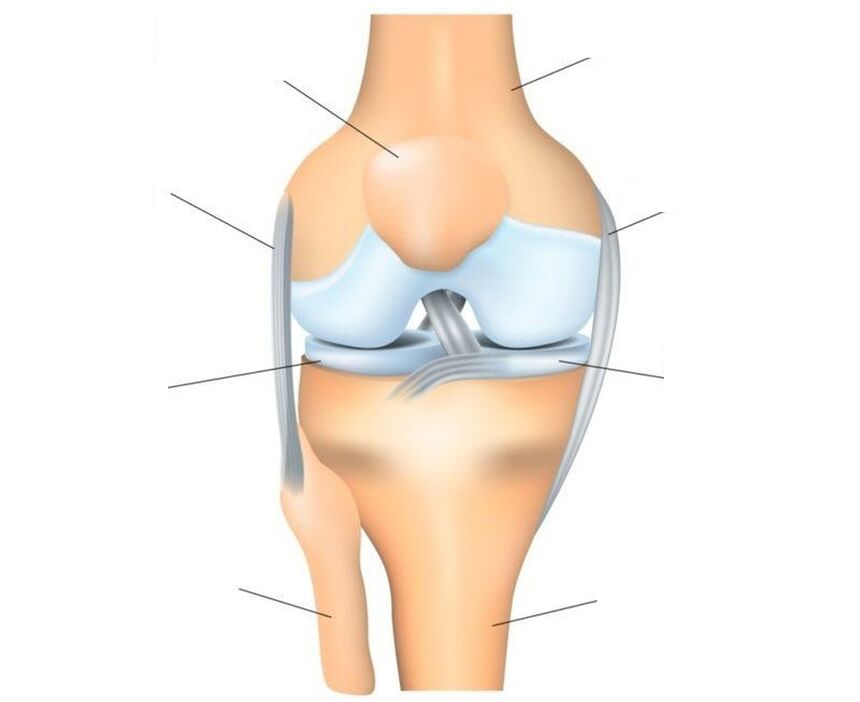

L'articulation du genou est l'articulation la plus complexe, car elle supporte la charge principale. Structure : trois os (fémur, tibia et rotule forment une seule articulation trochléaire, constituée de deux articulations interconnectées : fémorotibiale (tibiofémorale) et fémoro-patellofémorale (patellofémorale).

La rotule est un os sésamoïde plat (supplémentaire dans l'articulation) qui se fixe à la tête du fémur, glisse dans sa rainure concave et fait office de bloc. Caractéristiques structurelles : la face antérieure de la rotule est recouverte de périoste, la face postérieure, reliée au fémur, est recouverte de cartilage hyalin. La rotule est renforcée par des ligaments : principal et latéral – vertical (supérieur et inférieur) et horizontal (latéral – interne et externe).

O transmet la force du muscle quadriceps fémoral aux formations musculo-squelettiques du bas de la jambe, assurant l'extension du bas de la jambe au niveau de l'articulation du genou. La surface des os formant les articulations est recouverte de cartilage qui agit comme un amortisseur. Des amortisseurs supplémentaires qui protègent l'articulation des blessures sont deux ménisques cartilagineux en forme de croissant situés entre le fémur et le tibia. L'articulation est maintenue dans sa bonne position par les ligaments, les tendons et la capsule qui l'entoure.

Les blessures et les maladies affectent divers tissus articulaires. Tous ne peuvent pas tomber malades. Ainsi, le tissu cartilagineux ne possède pas de terminaisons nerveuses et peut donc être détruit de manière imperceptible et sans douleur. Mais les ligaments et la membrane synoviale ont de nombreuses terminaisons nerveuses et en cas de blessure ou de processus inflammatoires, ils commencent immédiatement à réagir, ce qui se manifeste sous la forme d'une douleur intense. En cas de destruction importante du cartilage articulaire, la douleur peut être associée à l'implication du périoste, la couche externe de l'os qui a une bonne innervation, dans le processus.